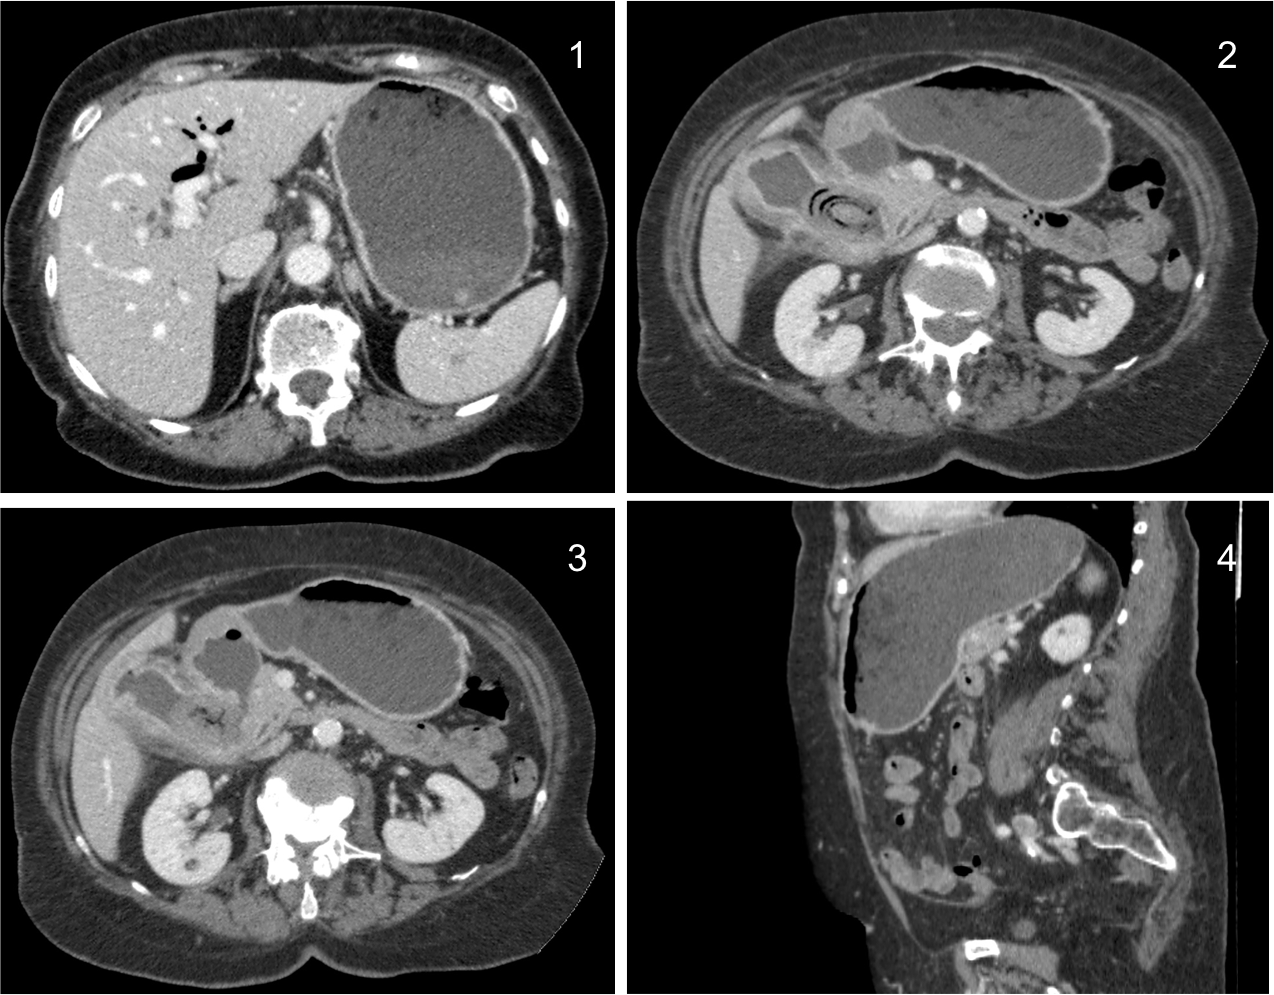

Triada de Rigler:

Otro caso: 1) Neumobilia + Dilatación de la cámara gástrica 2) Litiasis bilar + vesícula con proceso inflamatorio 3) Fístula vesiculo entérica 4) Dilatación de la cámara gástrica por obstrucción.